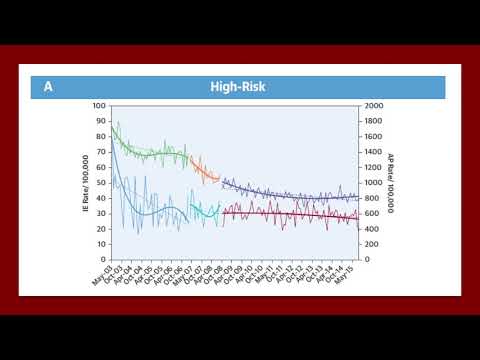

Profilaxis antibiótica e incidencia de EI antes y después de las recomendaciones de la AHA 2007. Dra. Ana Laura Mori. Residencia de Cardiología. Hospital C. Argerich. Buenos Aires